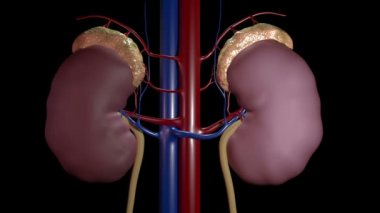

İnsanmikroSağlıkkanİlaçdikkatHastagövdeTedaviHastalıkbiyolojikanserbölümSistemAcıorgAyrıntılarkanaltaşlartüplerTeşhisanatomiBağışMikroskopfizyolojiNanoBöbreklerBöbrekİdrarfiltrasyonTümörmorfolojiiltihabımikroskopidonöriç organlara aitÜrogenitalÜrolojinefrithistolojiÜreböbreküstüDiyalizGlomeruluspiyelonefritnefronÜrologHematoksilenhydronephrosisurolithiasisBenzer İçerikler